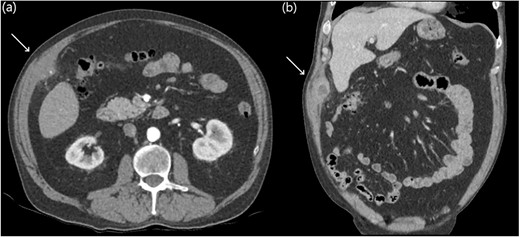

Eight years later, a computer tomography (CT) scan revealed a thick-walled collection on the deep aspect of the right anterolateral abdominal wall, adjacent to inferior hepatic segment 5 measuring 61 × 24 × 38 mm with a tiny focal calcific density (Fig. 1).

Abdominal CT axial slices (a) demonstrating a tiny focal calcific density in the right upper quadrant, and coronal slices (b) demonstrating a right upper quadrant intramuscular collection.